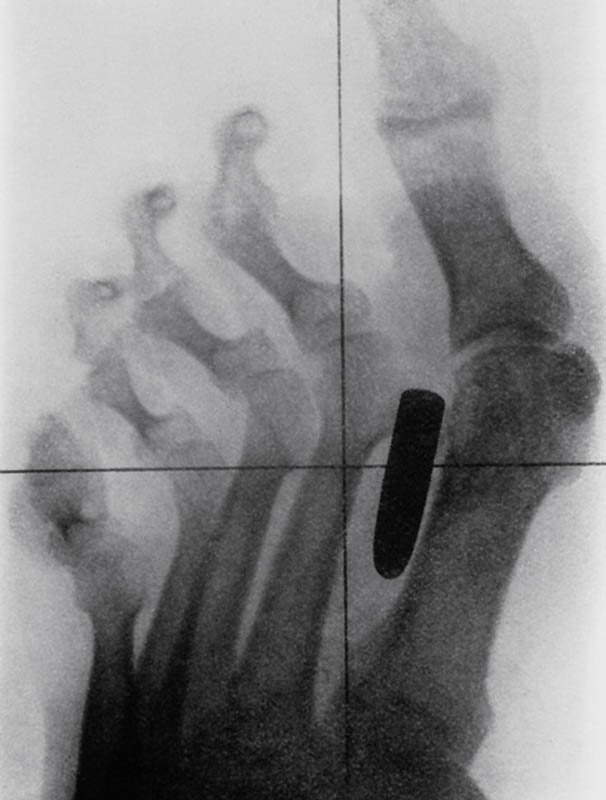

3. Старинный рентгеновский снимок ступни солдата англо-бурской войны (1899-1902) с огнестрельным ранением. Пуля застряла в плюсневой кости между большим и вторым пальцами.